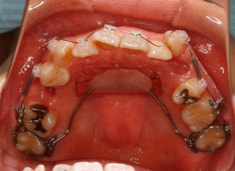

治療開始から約1年2ヶ月後